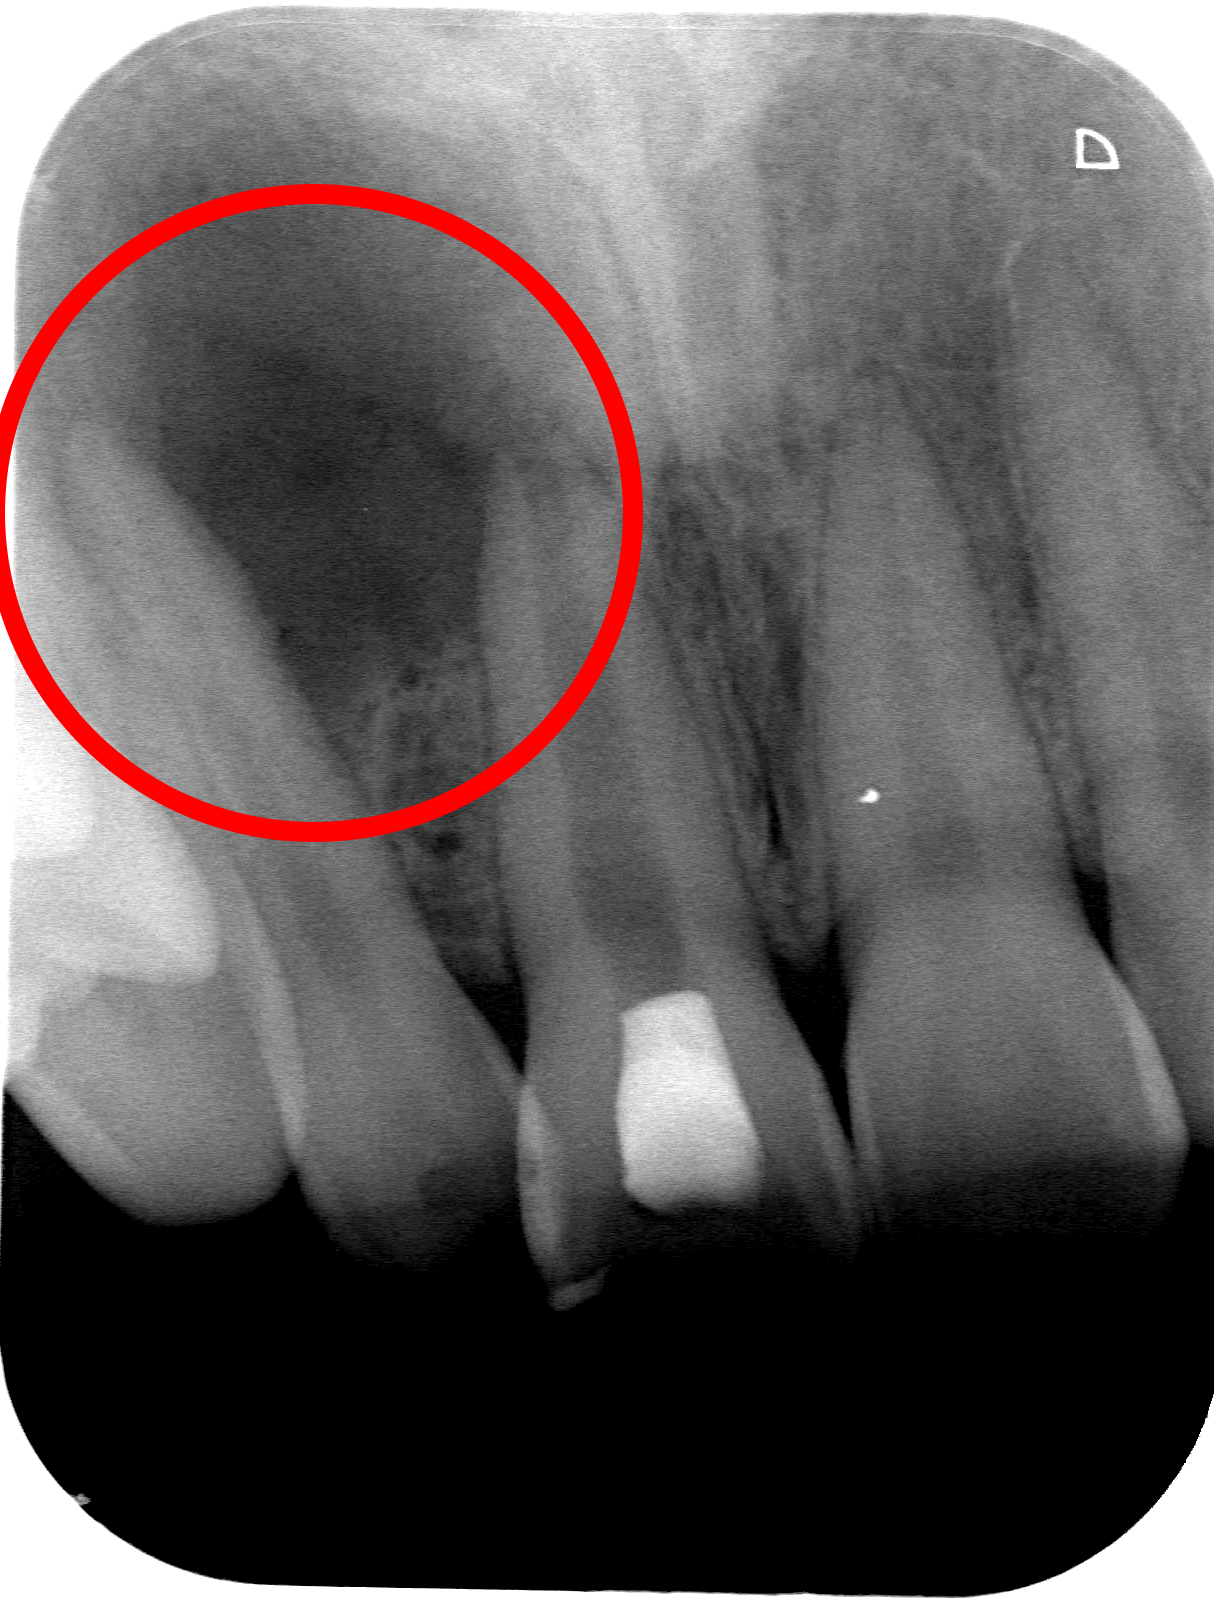

• 治療前

• 治療後

根の先の膿の袋が大きすぎて抜歯を宣告された症例。

当院では根管治療のみで、病変は完全に治癒した。